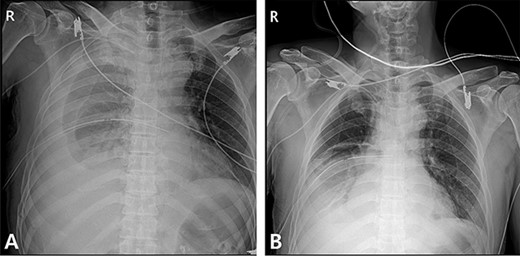

A 59-year-old man was admitted with multiple rib fractures and liver contusion due to a fall injury. He was standing on a chair for working at a farm, and it was knocked over causing him to fall and hit his flank against the corner of the chair. There was continuous pain while resting at the right flank and severe pain with pressure was noted, but no external wounds or bruises were observed. There were right 7th–11th rib fractures, scanty pneumothorax, minimal hemothorax and a 2-cm-sized liver contusion in abdomen and chest computed tomography (CT) scan (Fig. 1A, B). He was hospitalized for pain control and close observation in the general ward, and conservative management was initiated. Also, no significant changes were noted in the following daily follow-up chest radiographs. The patient suddenly complained of right-sided chest and back pain aggravation, cold sweating and fatigue 80 h after the traumatic injury. His mental status was alert, but v/s including systolic blood pressure (SBP) of 100–120 mmHg, heart rate (HR) of 40-60 beats/min and oxygen saturation of 100% during the admission changed to an SBP of 86/60 mmHg, HR of 88 beats/min and oxygen saturation of 97% when the symptoms occurred. Chest radiography was performed after the patient experienced aggravated symptoms, such as right-sided flank pain, cold sweating and fatigue. Compared to the previous scans, signs of increased opacification and peribronchial and parenchymal infiltrations were observed, which were indicative of hemothorax (Fig. 2A, B). We performed enhanced dynamic chest CT to identify any presence of active bleeding. On the chest CT scan, a large amount of hemothorax was identified in the right lung field along with multiple fractures of the right ribs. However, there were no signs of contrast leakage indicative of active bleeding (Fig. 3). Hemoglobin levels decreased from 13.1 g/dl on the day before the symptoms appeared to 11.5 g/dl at the onset of symptoms and to 9.4 g/dl after 2 h. Four packs of RBC transfusion and fluid were administered to the patient, and he was moved to the intensive care unit for close monitoring. And tube thoracostomy was performed, and 1600 ml of fresh blood was drained (Fig. 4A). The following day, 500 ml of blood was drained through the chest tube, but his v/s were stable (Fig. 4B). The amount of bleeding through the chest tube was decreased, but the drained fluid was fresh blood. And we thought that the remaining hematoma was not effectively drained, so the patient’s respiratory discomfort could persist and cause uneffective ventilation. And then we consulted with the Department of Thoracic Surgery, and video-assisted thoracoscopic surgery (VATS) exploratory thoracotomy was performed to identify the bleeding source caused by displaced rib and evacuate the large amount of hematoma. There was a large volume of hematoma within the pleural space and between the right lower lobe, diaphragm and fissure, but no active bleeding point was located. The fractured right 10th rib pierced through the pleural space and was displaced to the thoracic cavity, which was easily reduced. There was no injury surrounding the diaphragm, and although the general lung and chest wall contusions were severe, there were no signs of lung parenchymal lacerations (Fig. 5A–C). Chest tube drainage was serous, and there was no further bleeding. There were no signs of bleeding or any other abnormal findings on chest CT performed at the outpatient clinic, and the patient had no complaints of any symptoms (Fig. 6A, B).

Radiographic findings. (A) Initial chest X-ray showed no evidence of hemothorax. (B) Initial chest CT also showed no evidence of hemothorax.